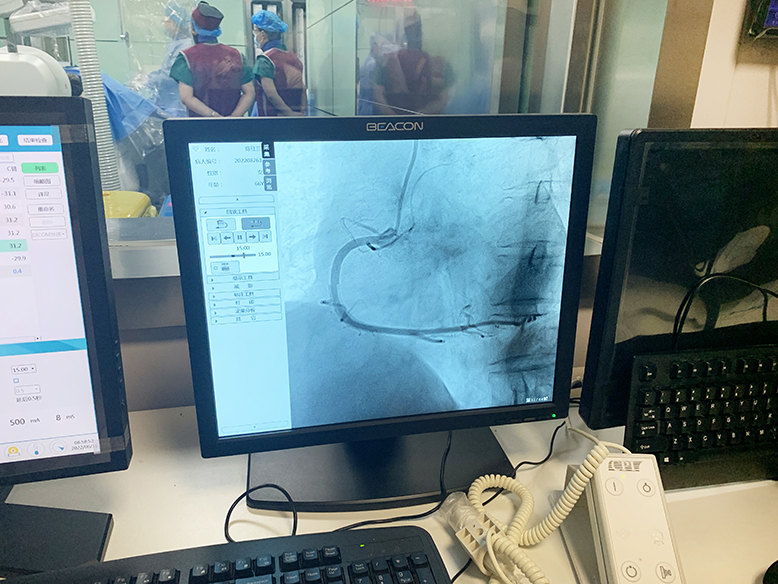

2022年6月16日,滨海新仁慈医院在郑州大学介入治疗研究所的技术支持下,成功实施了两例冠状动脉造影术(DSA),标志着该院在心血管疾病的治疗上迈上了新台阶。

经术前充分准备,上午8时手术顺利开始。介入导管室内,两位医师紧张有序地操作,术中患者情况稳定。上午9时许,在郑州大学第二附属医院专家和滨海新仁慈医院介入导管室团队的不懈努力下,手术顺利完成。术后,患者无任何不良症状,安返病房。

据滨海新仁慈医院介入导管室主任辛达路介绍,冠状动脉造影术是诊断冠心病的“金标准”。通过冠状动脉造影,可以了解冠状动脉血管分布,发现冠状动脉是否有狭窄以及血管狭窄程度。根据冠状动脉造影结果,决定是否对狭窄血管进行支架置入术或者冠状动脉搭桥手术治疗。